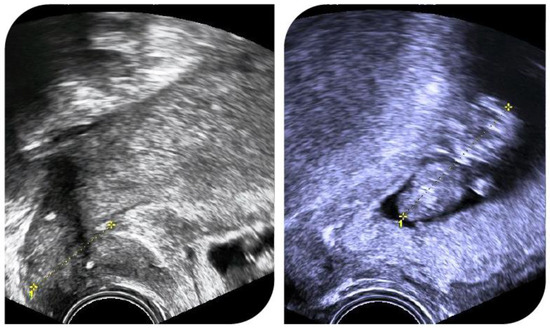

Background/Objectives: Obstetrical monitoring following radical trachelectomy (RT) for cervical cancer is marked by the lack of a standardized protocol, which may lead to delays in the intervention for cervical shortening. In light of the typical cervical remodeling process that occurs at the [...] Read more.

Background/Objectives: Obstetrical monitoring following radical trachelectomy (RT) for cervical cancer is marked by the lack of a standardized protocol, which may lead to delays in the intervention for cervical shortening. In light of the typical cervical remodeling process that occurs at the onset of labor, we hypothesized that the onset of premature cervical shortening in patients who have undergone radiotherapy commences at the internal ostium. Methods: We introduced the concepts of internal distance (distance between internal cervical ostium and cerclage thread) and the latent shortening of internal distance, which is characterized as a painless reduction in the internal distance, serving as an early marker of preterm contractions, thus enabling timely tocolytic intervention. Results: Three patients spontaneously conceived after RT. They were obstetrically followed-up after RT, using a combined approach of transvaginal ultrasound cervical markers and cardiotocography. Active tocolysis was used if internal distance shortening was observed. All patients delivered term healthy babies. Conclusions: The consistent ultrasound evaluation of both internal and external distances permits the proactive diagnosis of premature contractions and enables swift therapeutic measures. Full article

Show Figures

Figure 1